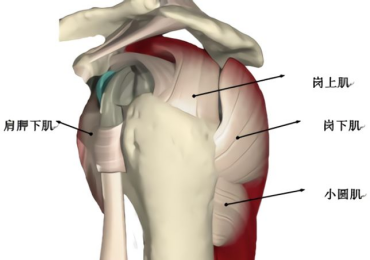

肩袖损伤又叫肩袖创伤性肌腱炎,其原发性问题主要出现于肩峰撞击导致肩袖肌腱损伤,后又继发滑囊炎,可引起肩关节疼痛和活动障碍,严重影响患者的生活质量。

(4)MRI:行MRI检查出现肩关节韧带损伤、肿胀、撕裂可确诊;